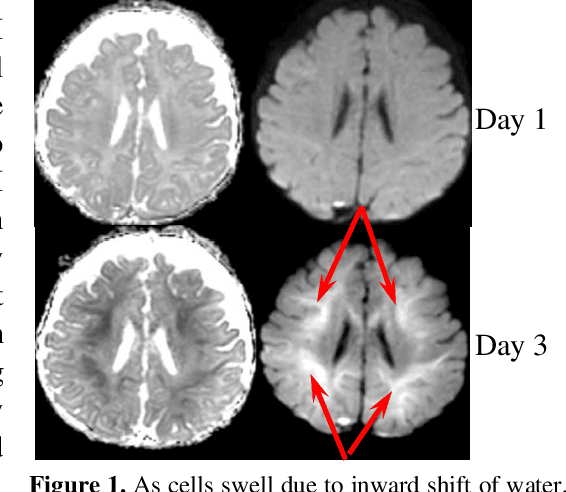

Abstract:This paper presents a deep learning framework for image classification aimed at increasing predictive performance for Cytotoxic Edema (CE) diagnosis in infants and children. The proposed framework includes two 3D network architectures optimized to learn from two types of clinical MRI data , a trace Diffusion Weighted Image (DWI) and the calculated Apparent Diffusion Coefficient map (ADC). This work proposes a robust and novel solution based on volumetric analysis of 3D images (using pixels from time slices) and 3D convolutional neural network (CNN) models. While simple in architecture, the proposed framework shows significant quantitative results on the domain problem. We use a dataset curated from a Childrens Hospital Colorado (CHCO) patient registry to report a predictive performance F1 score of 0.91 at distinguishing CE patients from children with severe neurologic injury without CE. In addition, we perform analysis of our systems output to determine the association of CE with Abusive Head Trauma (AHT) , a type of traumatic brain injury (TBI) associated with abuse , and overall functional outcome and in hospital mortality of infants and young children. We used two clinical variables, AHT diagnosis and Functional Status Scale (FSS) score, to arrive at the conclusion that CE is highly correlated with overall outcome and that further study is needed to determine whether CE is a biomarker of AHT. With that, this paper introduces a simple yet powerful deep learning based solution for automated CE classification. This solution also enables an indepth analysis of progression of CE and its correlation to AHT and overall neurologic outcome, which in turn has the potential to empower experts to diagnose and mitigate AHT during early stages of a childs life.